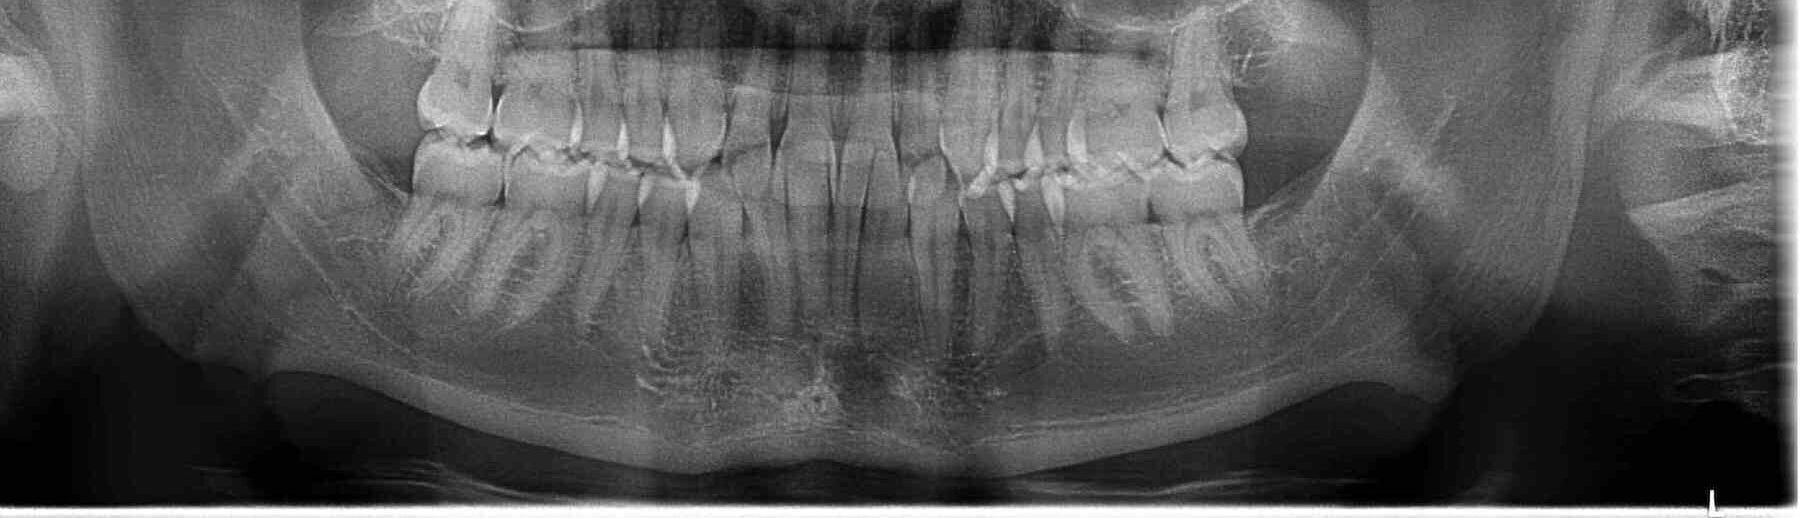

Extracción de terceros molares o “muelas del juicio”

Es una realidad que aproximadamente el 80% de las personas deben extraer sus terceros molares, ya sea por falta de espacio en la boca o bien para prevenir infecciones debido a la mal posición de sus muelas, lo que puede provocar mucho dolor sin un tratamiento adecuado. Si crees que lo necesitas, acude con nosotros para realizarte una valoración y prevenir cualquier complicación.

En Clínica Integral Odontológica tenemos el equipo necesario para tomar tu radiografía panorámica y especialistas en cirugía maxilofacial altamente calificados para resolver tus dudas y de ser necesario extraer tu terceros molares con la mayor seguridad posible.